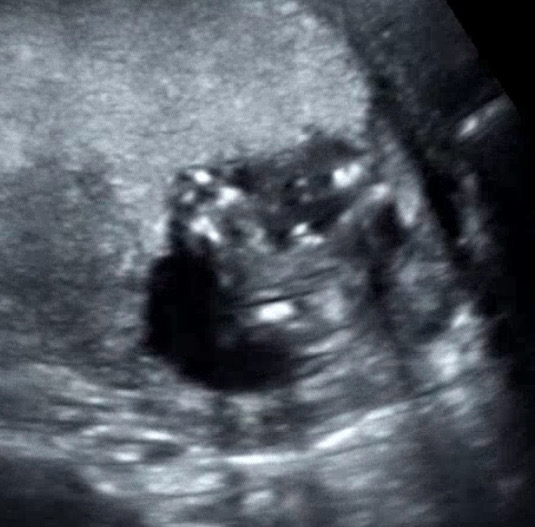

15주3일인데 성별봐주실분 있으실까요

오늘 성별을 알수있을까 싶어서 기대했는데 아기가 다리른 계속 양반다리자세로 있어서 정확히 모르겠다고 하시네요 ㅜ.ㅜ 양반다리하다가 살짝 벌린 찰라를 캡쳐했는데 뭘까용